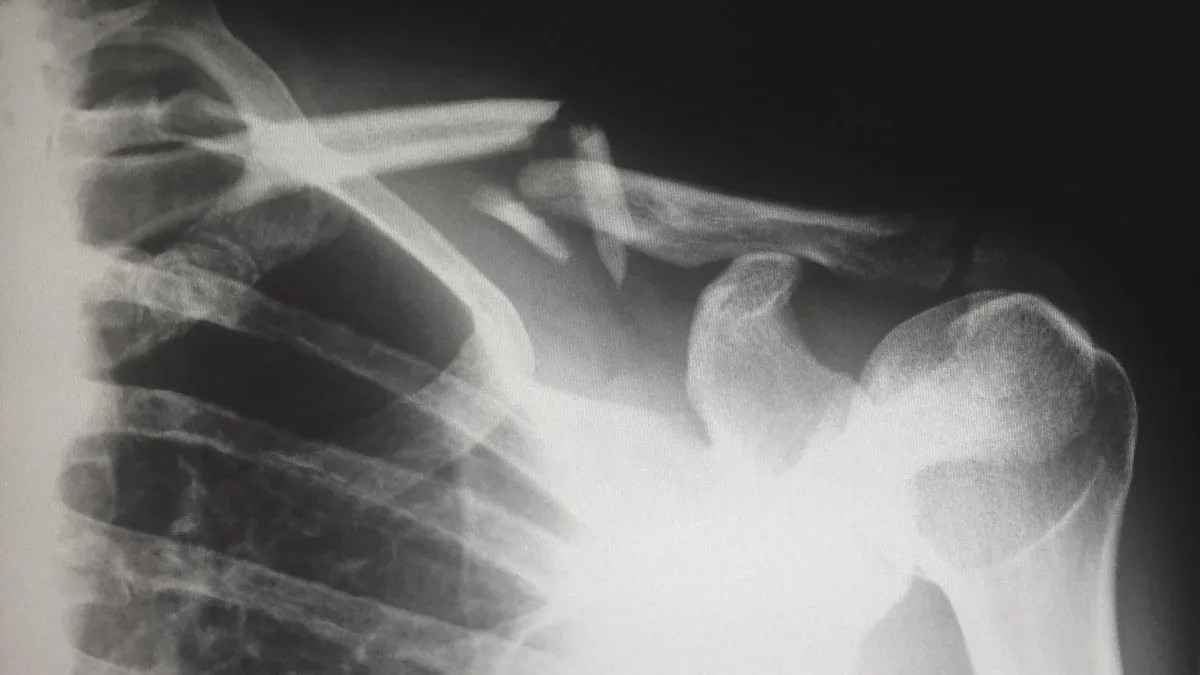

You may hear your doctor talk about an ac joint dislocation when you injure your shoulder. This injury happens at the acromioclavicular (AC) joint, where your collarbone meets the highest point of your shoulder blade. The joint helps your arm move and keeps your shoulder stable.

You might wonder when surgery becomes the best choice for an ac joint dislocation. Doctors use the Rockwood classification to decide if you need an operation. This system sorts injuries by how much the joint has moved and how unstable your shoulder feels.

If you have a mild injury (Type I or II), you usually do not need surgery. Rest, ice, and physical therapy help most people recover. For Type III injuries, your age and activity level matter. Young athletes or people with high physical demands may benefit from surgery. Types IV and V almost always need surgical repair because the joint is very unstable or out of place.